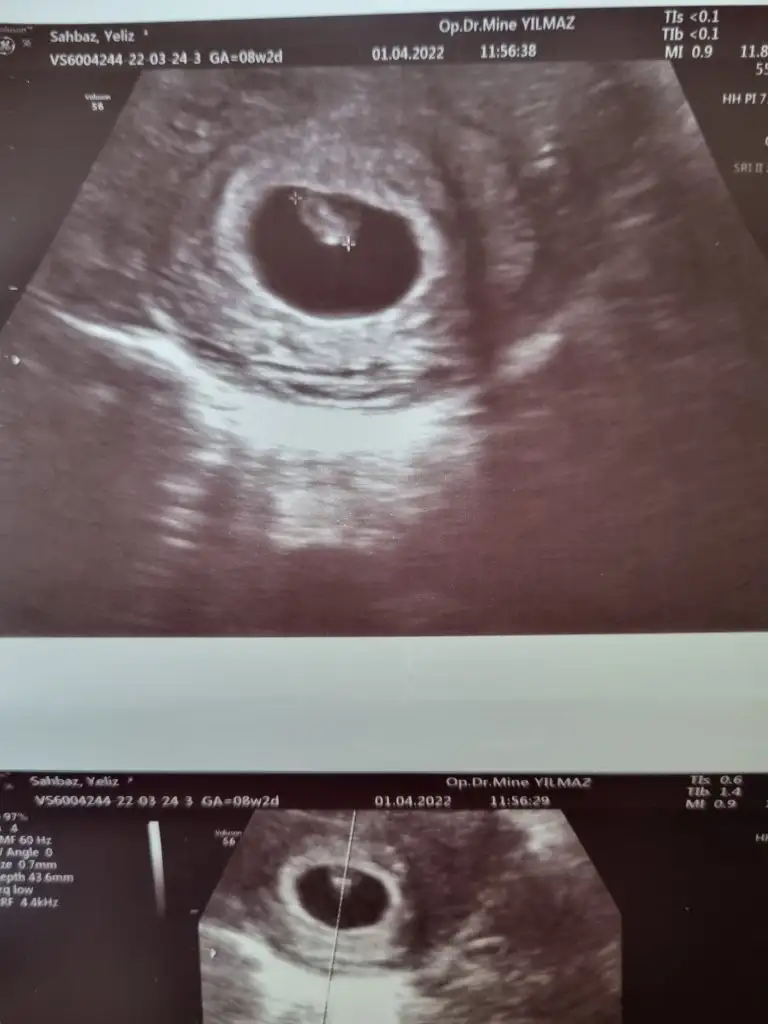

7+2 karındanSelam Kızlarbir çok kişi gruplardan beni bilir. Yine yetiştim imdatlara

Çoook uzun bir süre araştırma okuma yaptıktan sonra sizlere bu başlığı açtım çevremde tüm gebelere de denedim. Bunun sırrını çözen İnstagramda (isim vermeyim) işi ticarete dökmüş bile.Nub, Ramzi,Çin Rus Japon Takvimleri, Yüzük Yöntemi bir çok şey size sayabilirim.

5 ve 14. haftaya kadar olan ultrason fotolarınızı paylaşın. Vajinadan mı yoksa karından mı çekildiğini ve kaç haftalık olduğunu da mutlaka belirtin.

Not: Tahmin yaptığım anneler cinsiyet öğrendikten sonra lütfen bana geri dönüş yapın

merhaba diyim önce, bence erkek7+2 karından